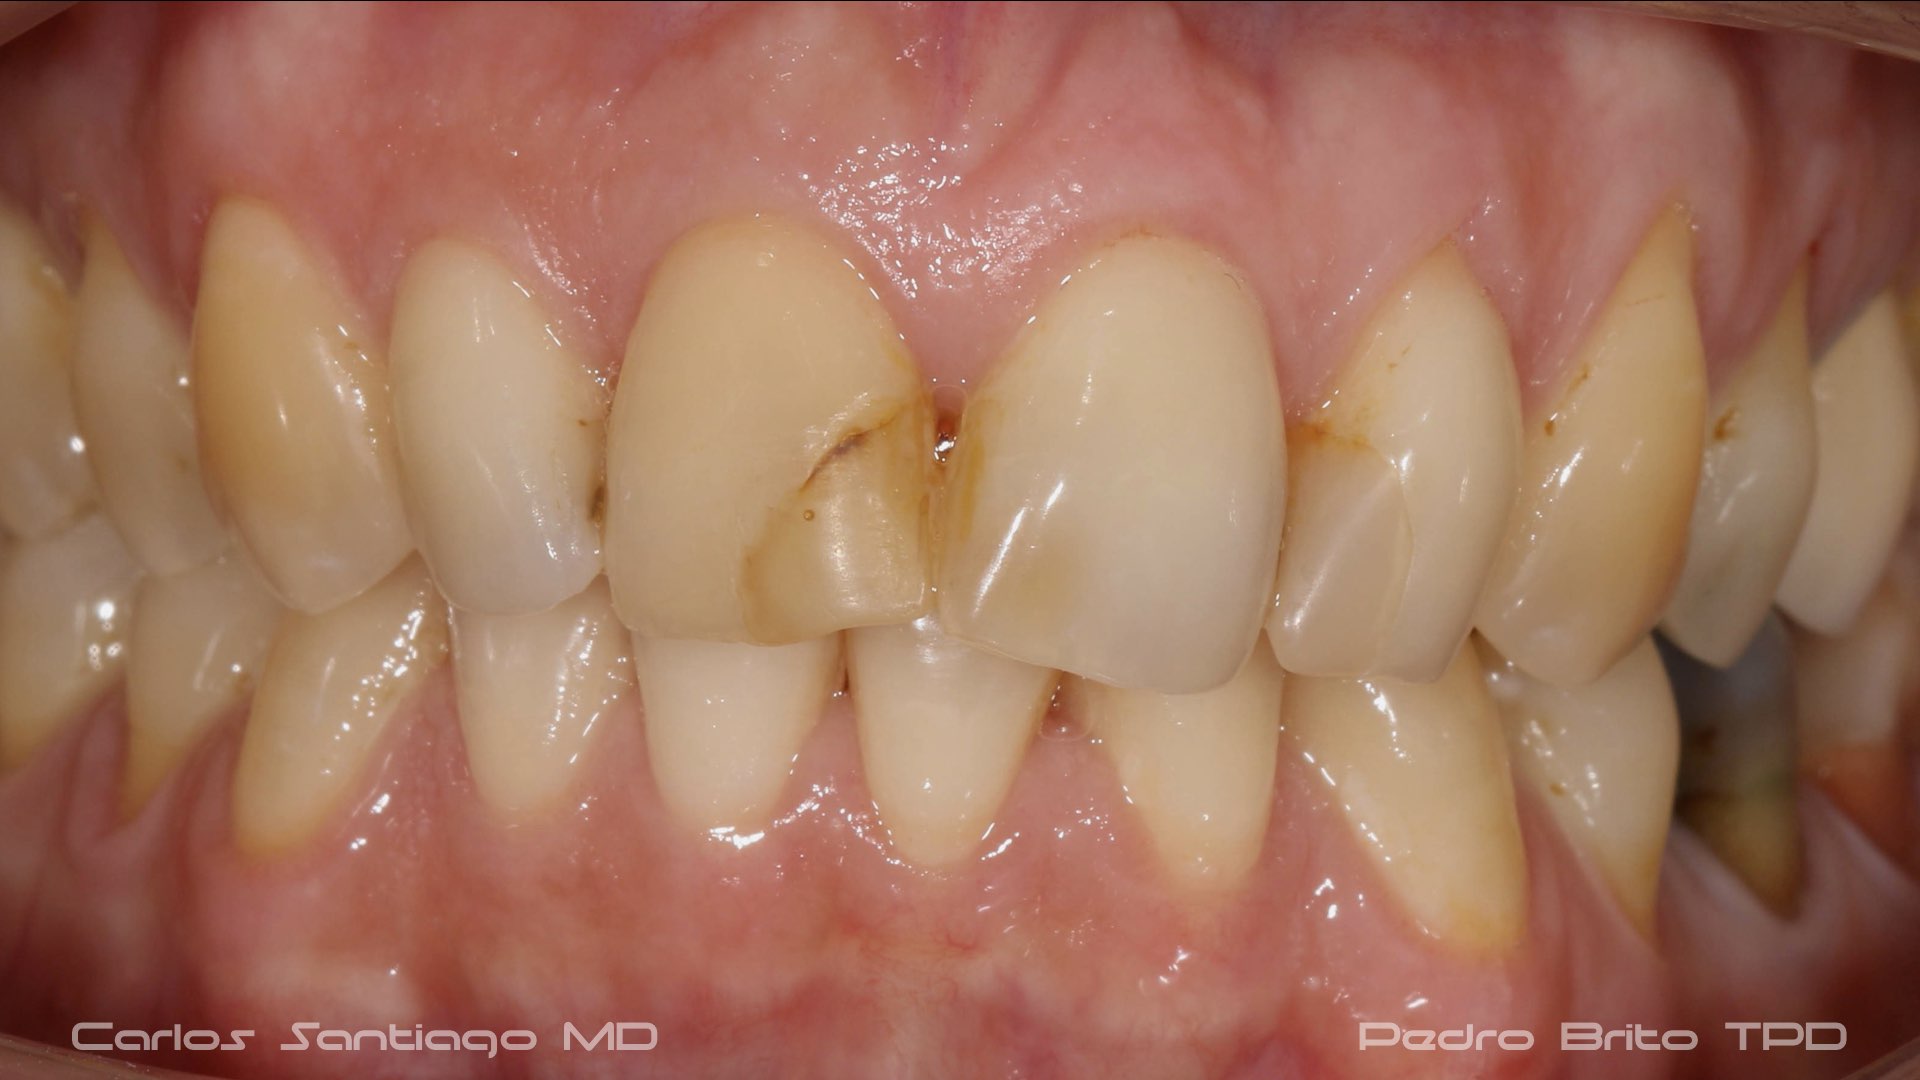

As Facetas Cerâmicas (lentes de contacto dentárias ou laminados), permitem corrigir da maneira mais estética e conservadora possível, problemas de forma e tamanho, côr e posição dos dentes, bem como substituir restaurações antigas e inestéticas.

São aderidas químicamente ao esmalte dentário de uma forma permanente, com o objectivo de melhorar a estética dos nossos pacientes.